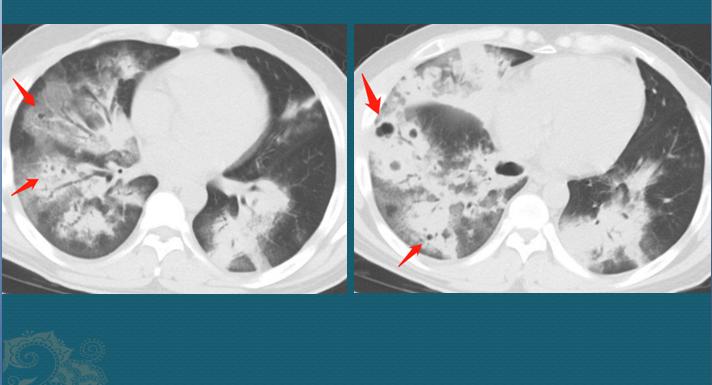

经过3天经验性治疗,这位病人症状没有缓解,复查了第二次CT:

白色病变区出现多发小空洞和小气囊(黑色)

CT片显示病灶进展、扩大,双肺多发斑片状影(重症肺炎),并且出现很多黑色小空洞和小气囊。这个时候CT就有了一定的特点,要考虑金黄色葡萄球菌肺炎。